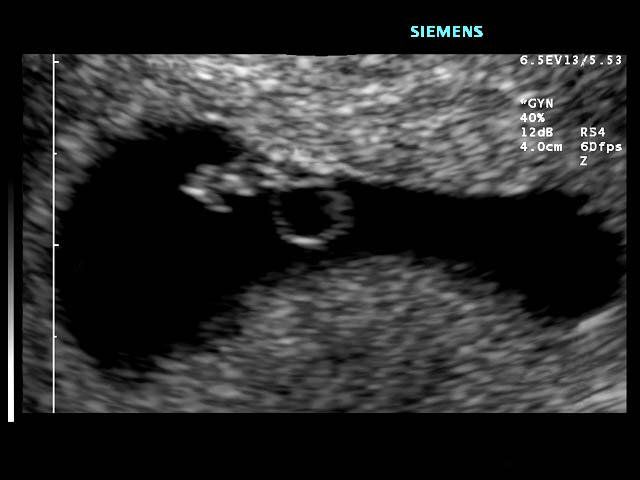

An approx. 12 week fetus, first ultrasound of this pregnancy.